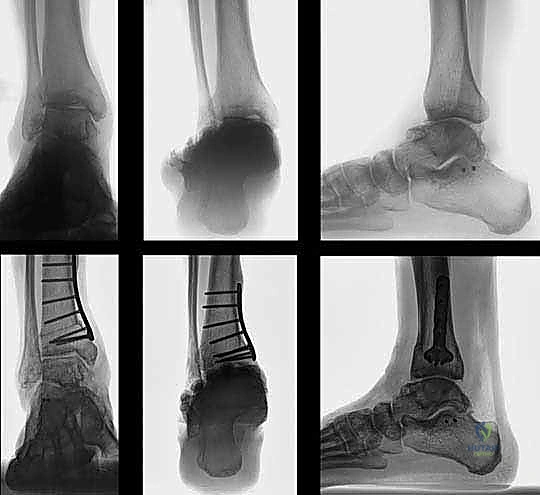

يُعد هذا من أكثر الأسباب شيوعاً في مجتمعاتنا. عندما يتعرض الشخص لكسر في عظم الظنبوب أو الشظية بالقرب من مفصل الكاحل، ولا يتم تجبيره أو تثبيته جراحياً بالزوايا التشريحية الصحيحة، يلتئم العظم في وضع معوج.

مثال سريري واقعي: مريض تعرض لكسر في الظنبوب والشظية قبل 26 عاماً، وتم علاجه بشكل تحفظي (بالجبس) دون تصحيح كامل للزاوية. بعد مرور ربع قرن، تطور لديه تشوه فحجي (تقوس للداخل) مع آلام شديدة نتيجة تآكل الغضروف الداخلي. في مثل هذه الحالات، قطع العظم هو الحل الجذري.

- الأشعة السينية أثناء الوقوف (Weight-Bearing X-rays): هذه هي الخطوة الأهم. لا يمكن تقييم تشوه الكاحل بدقة والمريض مستلقٍ. يجب أخذ صور أشعة طويلة للساقين بالكامل لتحديد "محور التحميل الميكانيكي" وقياس زوايا التشوه بدقة متناهية (مثل زاوية TAS وزاوية TLS).

- التثبيت الداخلي (Internal Fixation): بمجرد الوصول للزاوية المثالية، يتم تثبيت العظم في وضعه الجديد بقوة باستخدام شرائح معدنية متطورة (Locking Plates) ومسامير من التيتانيوم. هذا التثبيت القوي يضمن عدم تحرك العظم أثناء فترة الالتئام.